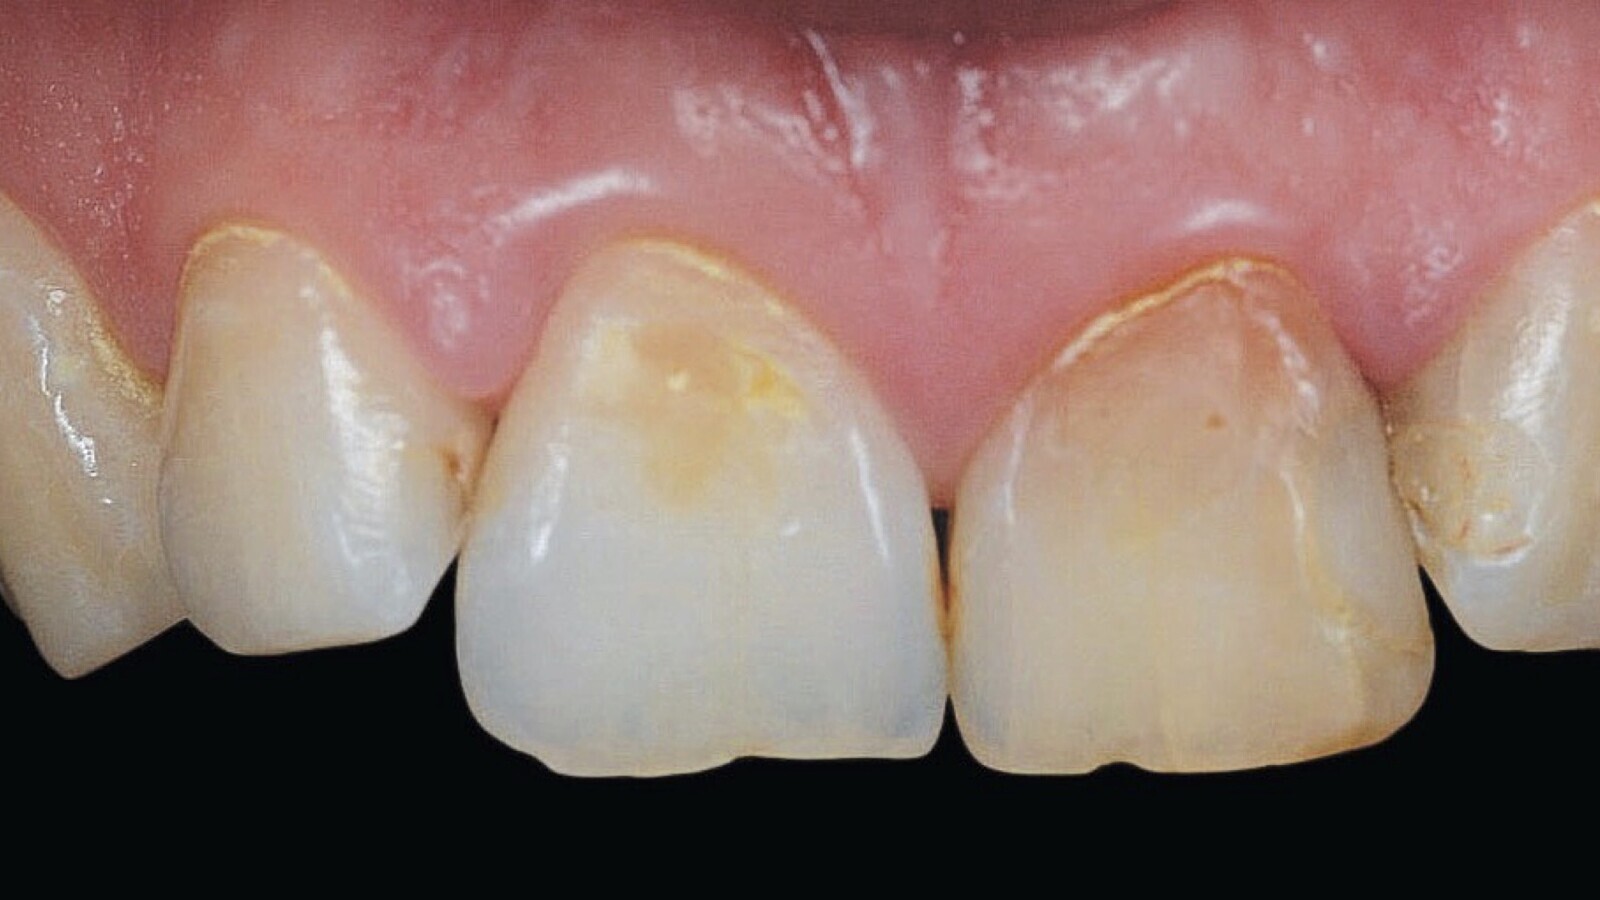

Severa alteración de color en un diente anterosuperior, que el autor trató mediante blanqueamiento dental.

Figura 1A. Desarmonía óptica visible en el diente 1.1.

Figura 1B. La desarmonía de la imagen superior fue solucionada mediante un tratamiento de blanqueamiento combinado.